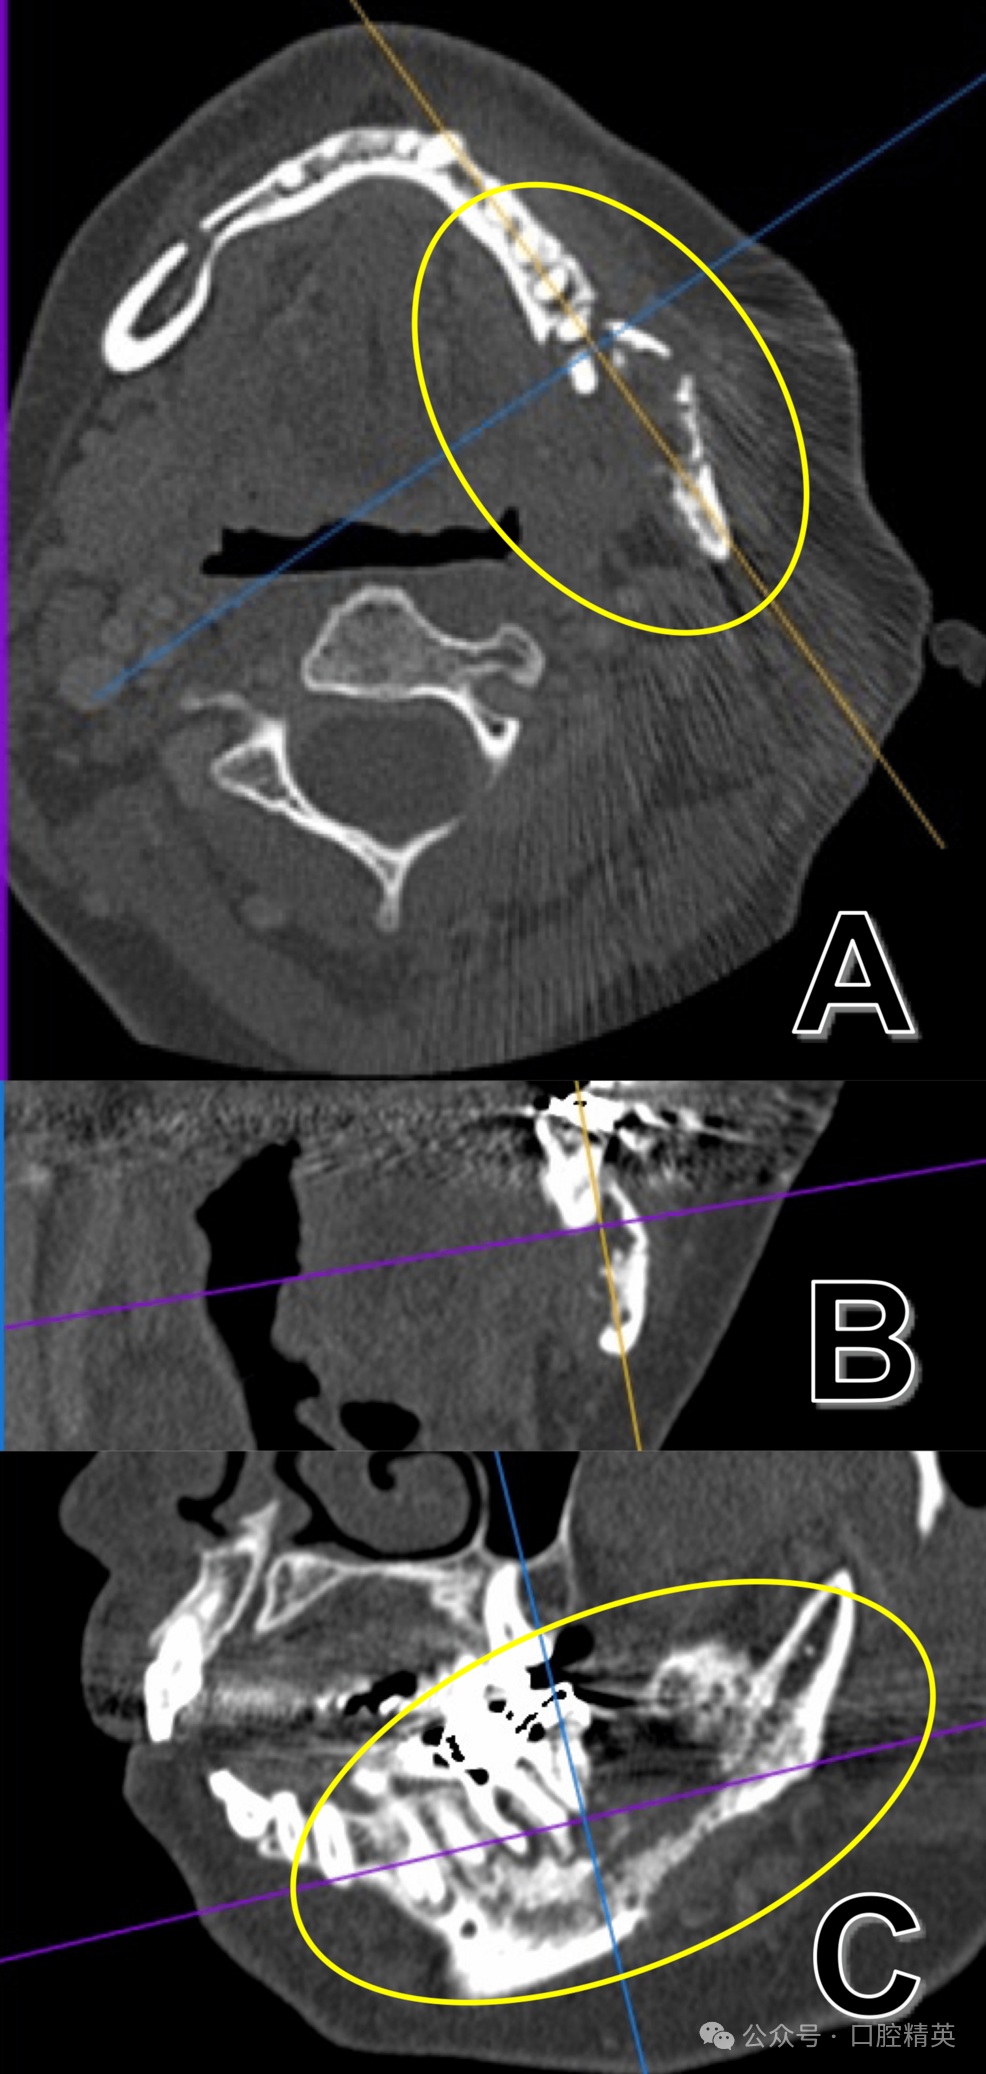

术后曲面体层片显示,38邻近区域及下颌骨下缘骨吸收显著(图4)。

图4 38拔牙后曲面体层片

可见38邻近区域及下颌骨下缘明显骨吸收(黄圈示较术前骨破坏进展,提示非典型下颌骨骨髓炎)。

CT进一步证实舌侧骨皮质吸收并侵犯下颌管(图5)。

图5 38拔牙后CT(硬组织模式)

(A)、冠状位(B)、矢状位(C)影像可见舌侧骨皮质不规则破坏性吸收并侵犯下颌管(黄圈示较术前舌侧骨皮质破坏进展)。